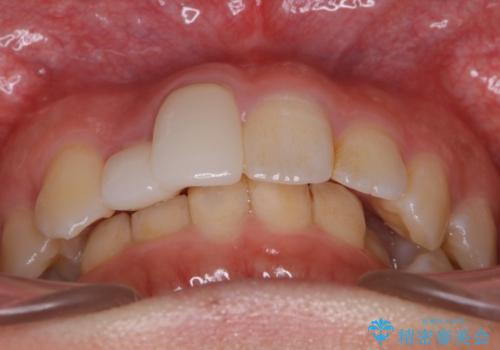

- 前歯の並びを気にして来院。

右上の2番目の前歯のセラミックが小さく、並びが気になるとのことでした。

右上の2番目の前歯が奥に入っている状態で、かぶせてあったため左に比べて短いセラミックになってしまっていました。

矯正治療で根の向きも修正したため、左右対称に審美的なセラミックを入れることができました。